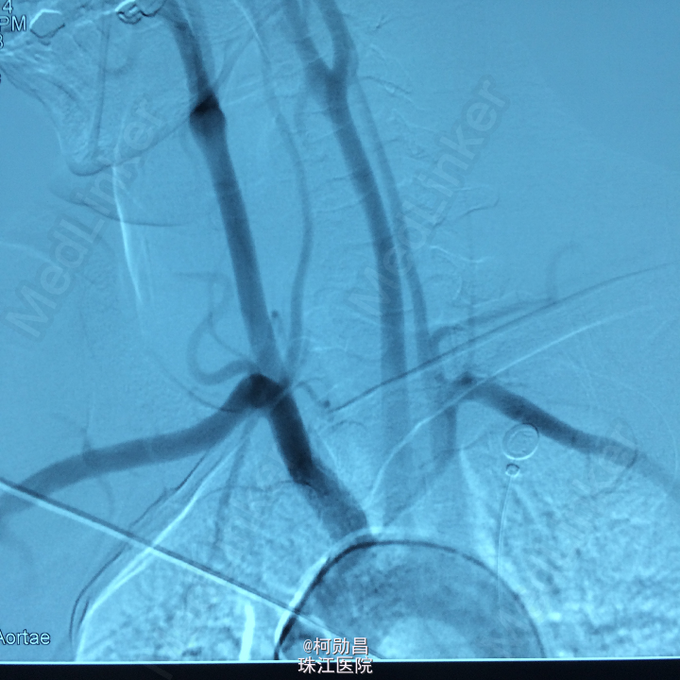

诊断:左侧顶叶占位 处理:行DSA检查,提示肿瘤染色,予PVA颗粒行血管内栓塞治疗。

术后再予开颅手术治疗,书中见供血动脉闭塞,出血量少。